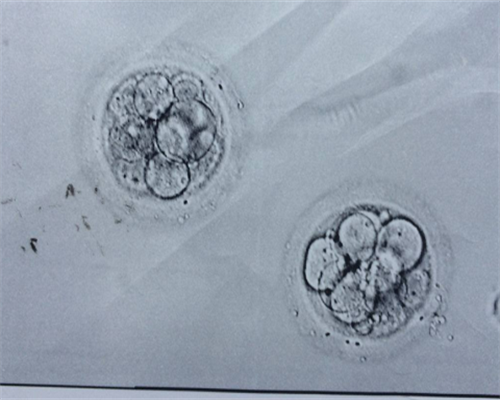

但是从试管婴儿角度这一方面大家一定要记住,因为试管婴儿的技术,尤其是第3代试管婴儿技术,本身就是对胚胎或者是基因进行染色体筛查这种情况下是完全可以选择*别的,也就是说从技术角度来看的话,选择*别对我们而言有至关重要的作用,甚至我们在选择*别的过程当中,要结合实际情况来进行综合的分析,只有这样才能给我们带来更好的选择保障。当然我们如果要选择试管婴儿手术的话,那么建议大家最好还是能够到医院先进行检查。

成都试管可以选性别吗?公立医院是不能进行性别选择的;要在国内做三代的要求十分严格,并非每个人都可以做,需要符合一定的要求家庭才能选择做三代,比如夫妻双方其中一人染色体异常、夫妻双方其中一方有家族遗传病史等。

三代可以,因为三代有胚胎筛查技术,可以看到胚胎内的染色体情况,既可以筛查出不健康胚胎,也可以选性别,这也是不少朋友二胎

选择

做三代试管的主要原因。